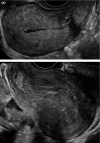

Purpose: To evaluate the reliability of the sonographic subserosal hypoechoic rim sign and endomyometrial junction indistinctness in distinguishing patients with acute puerperal endometritis from other common postpartum complications, particularly those with retained products of conception.

Results: The average sensitivity and specificity for readers identifying the subserosal hypoechoic rim sign in full-term postpartum patients with acute endometritis were 76.9% and 92.1%, respectively. Interobserver reliability was moderate with a kappa value of 0.5. The average sensitivity and specificity for endomyometrial junction indistinctness were 89.0% and 95.2%, respectively, with substantial inter-observer agreement, Kappa 0.7. These signs remained specific but were less frequently observed in postpartum patients scanned during early pregnancy.

Conclusion: We have shown that identifying the subserosal hypoechoic rim and endomyometrial junction indistinctness on ultrasound scans can reliably help to distinguish patients with acute postpartum endometritis from other complications, particularly in full-term postpartum patients.